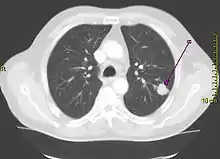

Performing a chest radiograph is one of the first investigative steps if a person reports symptoms that may be suggestive of lung cancer. This may reveal an obvious mass, the widening of the mediastinum (suggestive of spread to lymph nodes there), atelectasis (lung collapse), consolidation (pneumonia), or pleural effusion.[15] CT imaging of the chest may reveal a spiculated mass which is highly suggestive of lung cancer, and is also used to provide more information about the type and extent of disease. Bronchoscopic or CT-guided biopsy is often used to sample the tumor for histopathology.[13]

Lung cancer often appears as a solitary pulmonary nodule on a chest radiograph. However, the differential diagnosis is wide. Many other diseases can also give this appearance, including metastatic cancer, hamartomas, and infectious granulomas caused by tuberculosis, histoplasmosis or coccidioidomycosis.[65] Lung cancer can also be an incidental finding, as a solitary pulmonary nodule on a chest radiograph or CT scan done for an unrelated reason.[66] The definitive diagnosis of lung cancer is based on the histological examination of the suspicious tissue[2] in the context of the clinical and radiological features.[12]